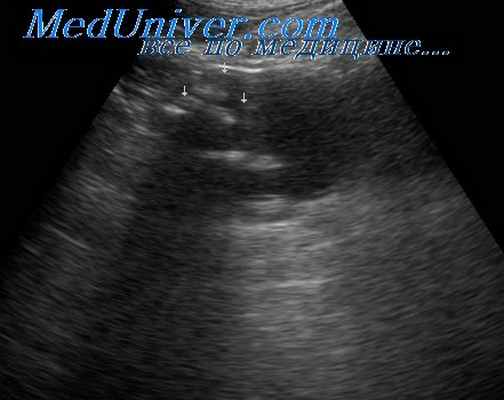

Ультразвуковое исследование почек выявляет участки воспаления, расширение и сужение почечных клубочков и сосудов, изменения положения и размеров почек. Также проводится доплерографическое исследование сосудов почек для оценки кровотока в органе.